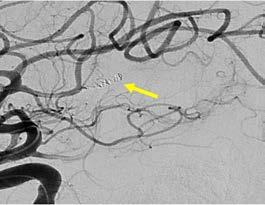

El día 18/2/2022 el paciente refiere dolor torácico. Se realiza un electrocardiograma, que muestra elevación del segmento ST en las derivaciones anteriores en relación con un infarto agudo de miocardio (IAM) anterior. Se activa código infarto y se realiza una coronariografía emergente, que muestra una oclusión de perfil embólico en la arteria descendente anterior media (Figura 1, flecha amarilla). Se trata con trombectomía aspirativa con buen resultado angiográfico final con flujo TIMI 3. Se inicia tratamiento con perfusión de heparina sódica. El día 19/2 el paciente comienza con cefalea muy intensa y afasia, por lo que se activa nuevamente código ictus y se realiza un angioTAC craneal que muestra una hemorragia subaracnoidea (HSA) de predominio izquierdo secundaria a sangrado por un aneurisma disecante de la rama M2 de la arteria cerebral media izquierda (Figura 2, flecha amarilla). Se decide completar estudio con una angiografía que confirma los hallazgos del TAC. Por el alto riesgo de resangrado y la necesidad de anticoagulación oral permanente, se decide embolización del aneurisma con coils, que resulta exitoso (Figura 3, flecha amarilla). Se reinicia durante el ingreso perfusión de heparina sódica y unos días antes del alta se comienza con anticoagulación oral con apixaban 5 mg/12 horas. La evolución clínica es favorable, siendo la exploración física al alta normal. Tras tres años de seguimiento bajo tratamiento con apixaban 5 mg/12 horas no han sido reportados nuevos episodios de sangrado ni de trombosis.

El caso presentado describe a un paciente de 61 años con FA de reciente diagnóstico, sin anticoagulación previa por un CHA₂DS₂-VA de 0, que desarrolla en pocos días tres eventos clínicos mayores: un ictus isquémico embólico, un IAM también de perfil embólico y una HSA secundaria a un aneurisma disecante en la rama M2 de la arteria cerebral media izquierda. Esta rara secuencia de eventos plantea un escenario clínico de extrema complejidad, donde el manejo antitrombótico, particularmente la indicación de anticoagulación oral, requiere una cuidadosa evaluación riesgo-beneficio.